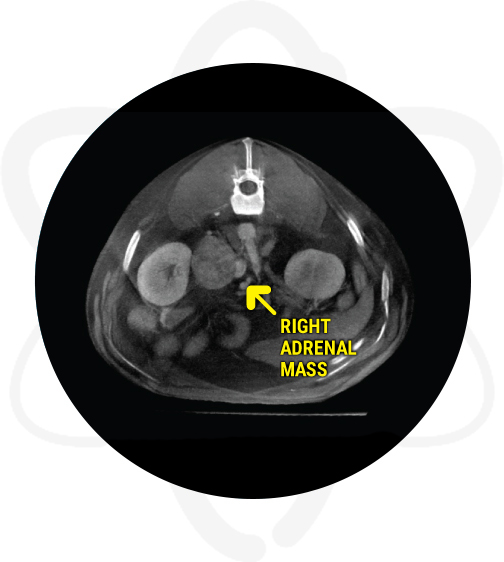

Patient is a 14 yr old, MN, retriever mix that presented for a brain CT due to recent onset of lethargy, ataxia, not eating well and abnormal behavior. In addition, a CT scan of the abdomen was requested due to an adrenal tumor found on ultrasound.

- Abdominal ultrasound revealed an enlarged right adrenal gland of mixed echogenicity, solid in appearance, irregular in shape but with no evidence of mineralization.

A large aggressive right adrenal mass invading the caudal vena cava and displacing the right kidney and renal vessels was noted on abdominal scan. The mass likely represents a neoplastic process such as adrenocortical carcinoma or pheochromocytoma vs neuroendocrine neoplasia. The slim left adrenal may be secondary to some degree of atrophy. No other evidence of metastasis was noted. In addition, there were portal vein filling defects which can be secondary to small thrombi or secondary to streamlining (artifact of flow).

Provided crucial information such as invasion into vena cava and displacement of right renal vessels regarding the previously known adrenal gland abnormalities.